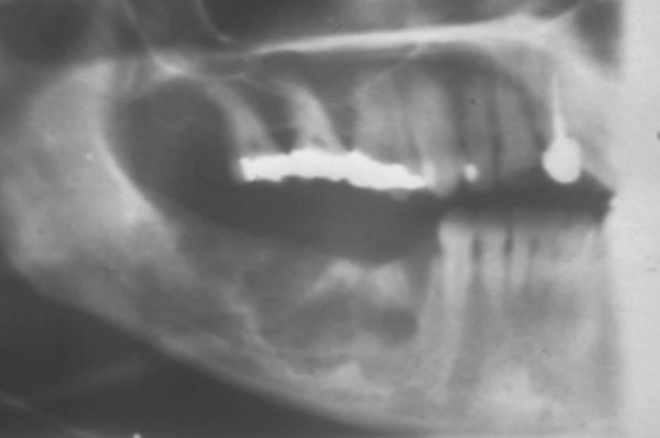

ill defined

how would you describe the BORDERs of this lesion